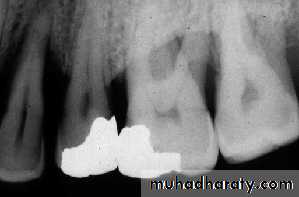

• B-Defective Restoration;

• Faulty dental restoration act as potential food traps & lead to the accumulation of food debris & bacteria.

• Radiographically; the defective filling identified with open or loose contacts, poor contour, uneven marginal ridges over-hangs.